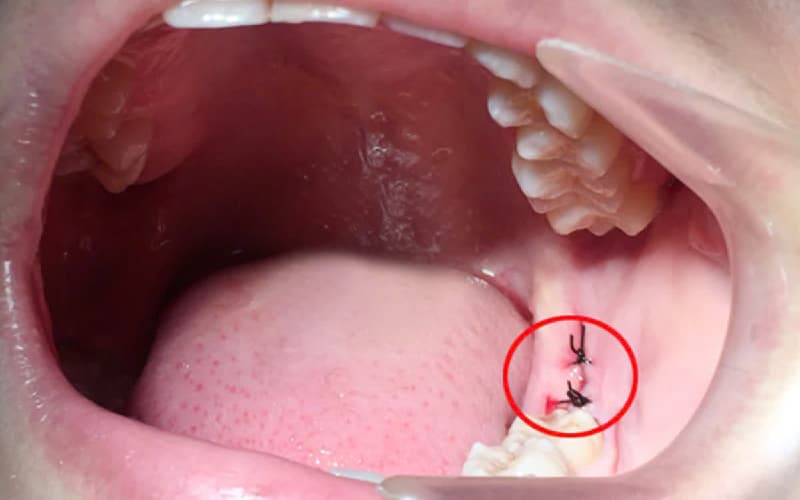

3.3. Biến chứng nguy cơ

Ổ răng khô (dry socket) là một trong những biến chứng phổ biến nhất sau khi nhổ răng khôn. Tình trạng này xảy ra khi cục máu đông trong ổ răng bị rơi ra hoặc không hình thành đúng cách, để lộ xương và dây thần kinh bên dưới. Người bệnh sẽ cảm thấy đau đớn dữ dội và có mùi hôi từ vùng phẫu thuật.

Nhiễm trùng cũng là một biến chứng cần được theo dõi chặt chẽ. Các dấu hiệu nhiễm trùng bao gồm sưng nề tăng dần, đau nhức lan rộng, sốt và có mủ chảy ra từ vết thương. Nếu không được điều trị kịp thời, nhiễm trùng có thể lan rộng và gây nguy hiểm đến tính mạng.